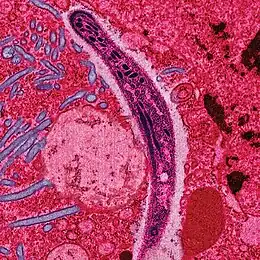

Un sporozoïte de Plasmodium se déplaçant dans le cytoplasme d'une cellule de l’épithélium de l'estomac (boyaux médians) d'un Anopheles stephensi. Micrographie électronique en fausses couleurs.

Le paludisme est causé par un parasite protozoaire du genre Plasmodium (Phylum apicomplexa). Chez les humains, le paludisme est essentiellement causé par P. falciparum (80 % des infections et 90 % des décès) et P. vivax[98],[112]. Trois espèces moins répandues et provoquant moins de symptômes peuvent également infecter l'être humain : P. malariae, P. ovale wallikeri et P. ovale curtisi[98].